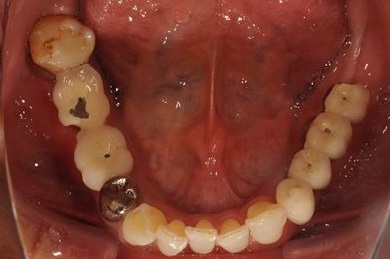

インプラントの症例写真 IMPLANT

骨再生インプラント治療

| 性別/年齢 | 男性 / 58歳 | ||||||||||||||||||||||||||||||||

| 主訴 | ブリッジがだめになったため、現在は部分入れ歯を使用しているが、インプラント治療を検討している。 | ||||||||||||||||||||||||||||||||

| 治療方針 | 左上奥の欠損部分をインプラント治療にて、機能的・審美的回復を行う。 | ||||||||||||||||||||||||||||||||

| 治療内容 | インプラント3本(GBR)、ハイブリッドセラミッククラウン3本 | ||||||||||||||||||||||||||||||||

| 総治療費 | 791,520円 | ||||||||||||||||||||||||||||||||

| 治療期間 | 10ヶ月 |